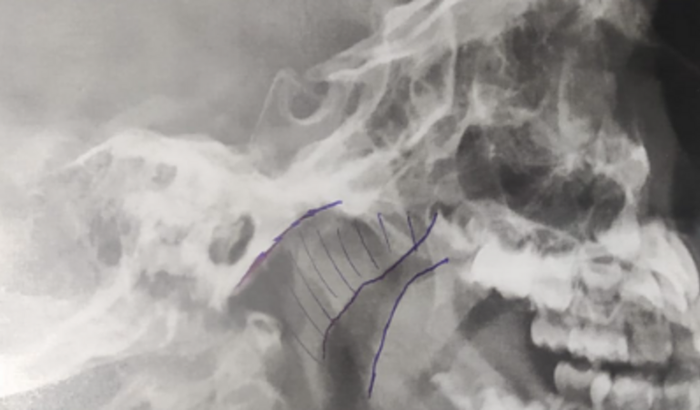

Me chamo Janaina e criei essa vaquinha para arrecadar dinheiro para fazer a cirurgia de adenoide da minha filha de 4 anos. No início desse ano de 2022 ela começou a desenvolver um quadro de sinusite, com dor nos ossos dos seios da face e recentemente na testa também. Desde então praticamente todos os meses tem tido quadros de febre, secreção no nariz e as dores. Os médicos vem tratado com antibióticos e corticoides, medicamentos que não vem demonstrado resultados a longo prazo, e sim somente durante o tratamento. Foi então que fiz uma consulta particular com a otorrinolaringologista Dra. Andrea Soccol, que solicitou exames de sangue e radiografia, onde na radiografia constou o aumento das adenoides com redução da coluna aérea rinofaringea. A Dra. então explicou que a adenoide está ocupando cerca de 80% do espaço da rinofaringe, além de a concha da narina direita estar aumentada, dificultando também a passagem do ar. Na radiografia ainda mostrou a presença de pus nos ossos dos seios da face. A Dra. Andrea pediu 9500,00 com as custas da equipe cirúrgica e do hospital, tenho o orçamento a punho dela. Pelo SUS é uma cirurgia demorada, e como ela está tendo crises constantes precisa fazer a cirurgia o quanto antes. Quem puder ajudar agradeço de coração e vou mantendo todos informados, prestando contas no final.